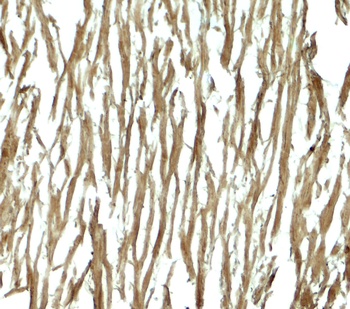

Immunohistochemistry of DNAJC13 in human heart tissue with DNAJC13 antibody at 5 µg/mL.